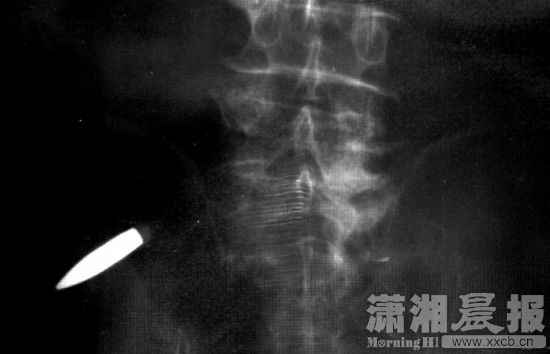

X光片上,一颗子弹的影像斜插在紧挨髋关节的大腿里。这颗被日军射出的子弹,隐藏在唐荫岳体内76年。图/潇湘晨报记者 陈正

1939年初夏,唐荫岳部队在山西省长子县修筑防御工事,日军发现后发起猛烈攻击,战斗持续一整天。休息时,战友发现唐荫岳裤子血迹斑斑。“我这才知道自己已经受了伤,这个时候才感觉痛。”此后,他被转到战地医院治疗,因当时医疗条件有限,擦着骨头存在腿内的子弹没能取出来。